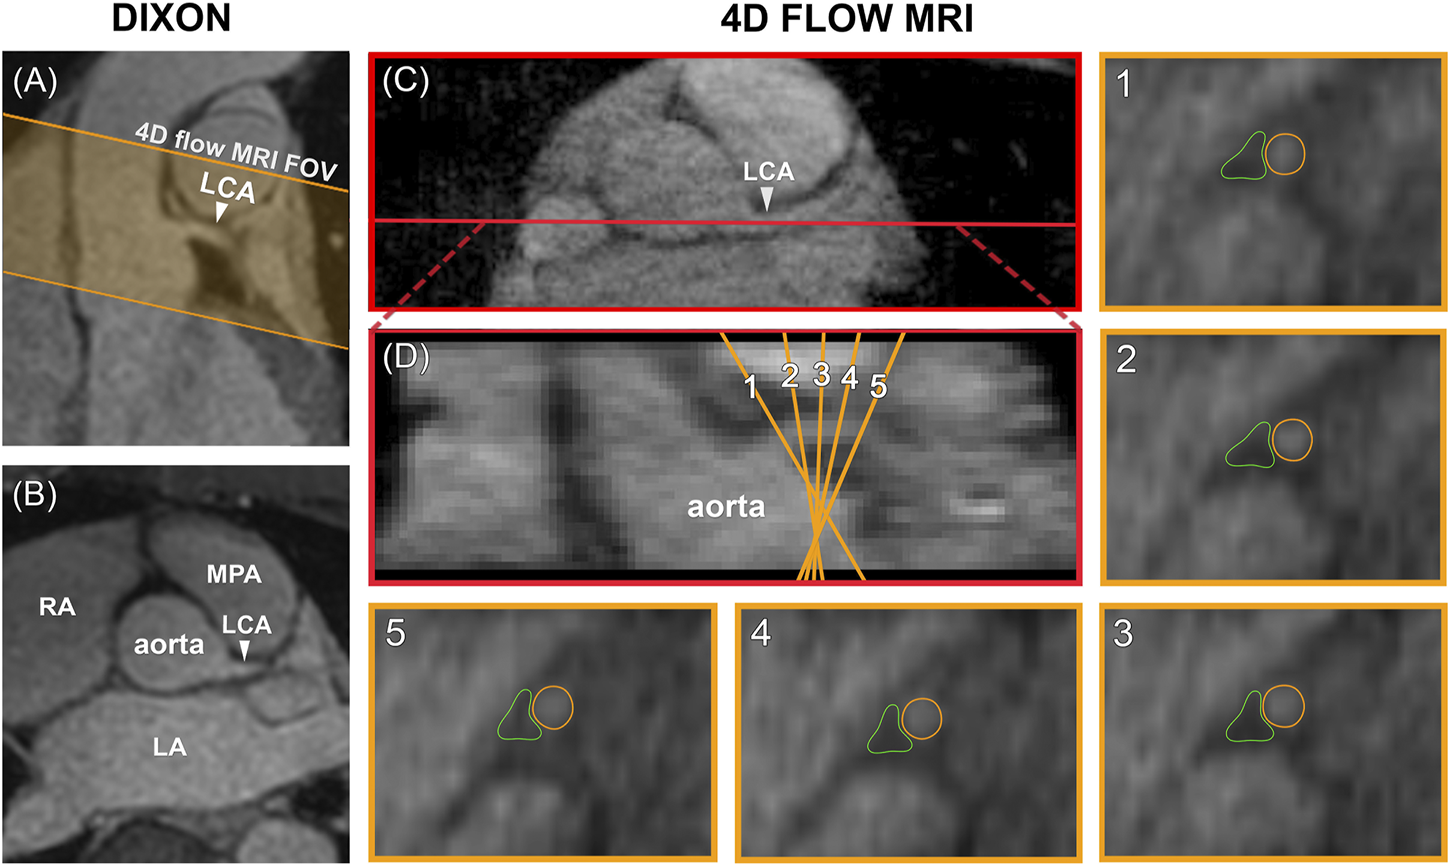

Data Analysis

Data analysis was performed in GTFlow V3.2.15 (Gyrotools, Zürich, Switzerland). 4D flow MRI magnitude images were used to localize the LCA branching off from the aorta in a mid-diastolic time frame and to make a longitudinal cross-section, see Figure 2. The longitudinal view was used to place 5 equidistant analysis planes perpendicular to the LCA, approximately 1.5 mm apart, to be able to check for consistency of the measurements over the length of the LCA. Next, the LCA was visually identified in each plane and measurement contours were drawn around the lumen. Additional reference contours were drawn in the adjacent pericardial fat to verify that the measurements would amount to zero flow here, see Figure 2. Both the LCA and the reference contours were copied to all mid-diastolic time frames and onto the corresponding velocity images. Other time frames in which the LCA could not be identified because of blurring due to myocardial contraction and relaxation were discarded. Diastolic flow curves were calculated for each contour, as well as streamlines for visualization. Contour-averaged flow curves were calculated for each subject and averaged over all subjects. For comparison with velocities reported in echocardiographic and 2D flow MRI studies, maximal velocity (VMAX) was determined for each contour and each time frame by selecting the voxel with the highest signal within the contour. Next, time-averaged diastolic VMAX and diastolic peak velocity (VPEAK) were determined for each subject.

FIGURE 2

www.frontiersin.org

FIGURE 2. (A) Planning of the 4D flow MRI field of view (orange) on the Dixon water image. (B) Transversal view of the Dixon water image. (C) The LCA is identified on a transversal 4D flow MRI magnitude image and a longitudinal cross-section is made (shown in red). (D) The resulting coronal view is used to place five analysis planes perpendicular to the LCA. 1–5) In these planes, measurement contours are placed around the LCA lumen and in adjacent pericardial fat. FOV = field of view, LCA = left coronary artery, LA = left atrium, RA = right atrium, MPA = main pulmonary artery.